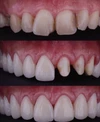

Zirkonyum uygulamalar

Porselen uygulamaları

Laminate veneer